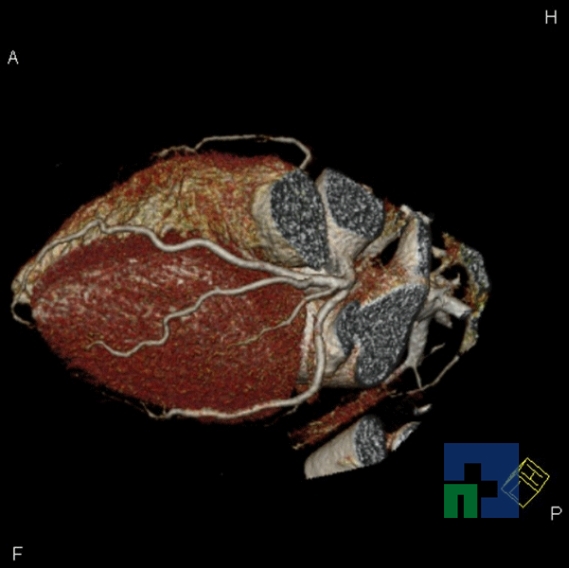

Examinare de rutină cerebrală, nativ și cu substanță de contrast (SDC) pentru diagnosticul:

- Tumorilor cerebrale

- Tumorilor cerebrale: